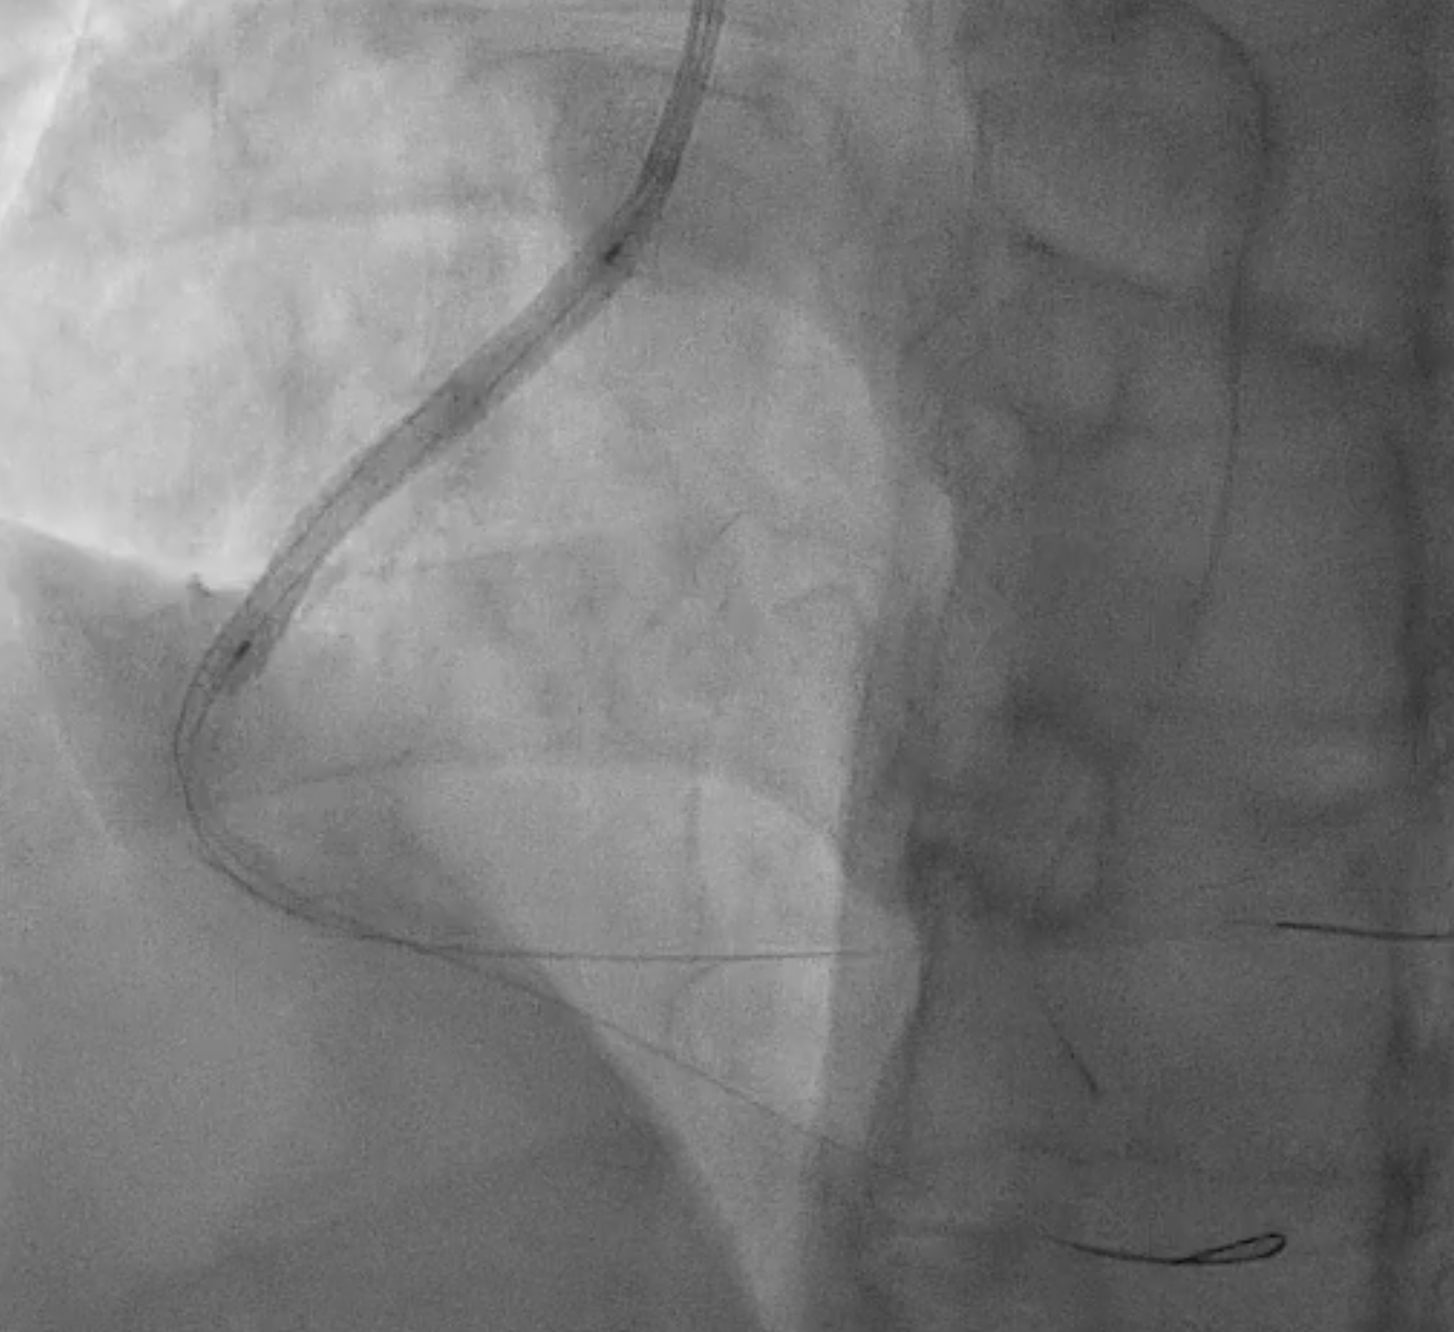

Because the patient presented with acute coronary syndrome, primary PCI was first performed for the culprit lesion, and a drug-eluting stent (DES) was implanted in the proximal LAD. A staged PCI with DES implantation to the proximal LCX was later performed. The initial antegrade attempt for RCA chronic total occlusion (CTO) failed despite wire escalations, as the guidewires could not cross the lesion. Considering the patient¡¯s intolerance and high contrast volume, the procedure was terminated. One month later, the patient was readmitted for complete revascularization. Antegrade wiring with a microcatheter and multiple guidewires (Fielder FC, ULTIMATEbros3, Conquest Pro) again failed to cross the RCA CTO. A retrograde approach using a SION wire via a septal collateral successfully reached the distal RCA. As the retrograde wire could not smoothly re-enter the true lumen, an antegrade wire was used to create a controlled subintimal hematoma, followed by the reverse CART technique. Anchoring balloon support then facilitated microcatheter advancement into the proximal RCA. The rendezvous technique achieved externalization with an ASAHI RG3 330 cm wire, and two Runthrough wires were advanced antegradely into the PDA and PL branches. After sequential balloon dilatation, two DESs (XIENCE Skypoint 2.75 ¡¿ 48 mm and 3.5 ¡¿ 38 mm) were deployed from the distal to the ostial RCA under IVUS guidance. Final angiography showed successful recanalization with TIMI 3 flow.